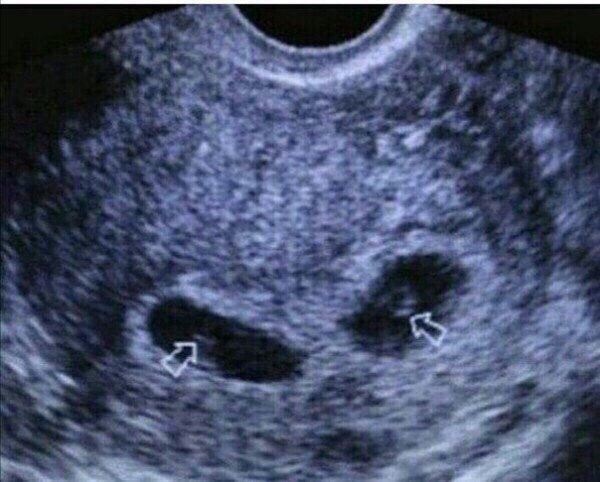

Эта зима застала нас врасплох, встретила приятным сюрпризом...эти два маленьких комочка лежат здесь на протяжении 8 недель..но мы ничего не знали, конечно по началу нас охватил шок, но мы все равно безумно рады🙏особенно от того, что их там двое, мы еще не узнали пол, мальчики или девочки, но мы бесконечно счастливы..На самом деле мы не знаем кто их родители, но ты можешь скопировать этот текст и подшутить над друзьями))))